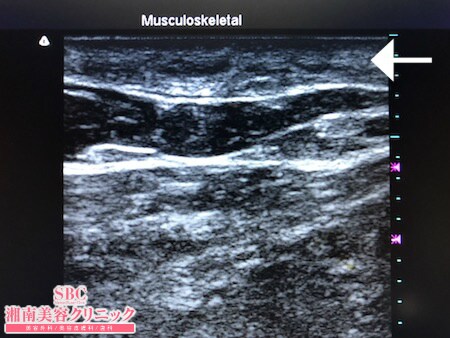

No.242307【脂肪吸引】【動画あり】湘南美容外科脂肪吸引最高責任者である竹田先生による脂肪吸引のフォトギャラリー!リピーターの患者様!太ももの脂肪吸引に大満足して今度はおなかの脂肪吸引を受ける!術中3Dタッチビュー・右腰